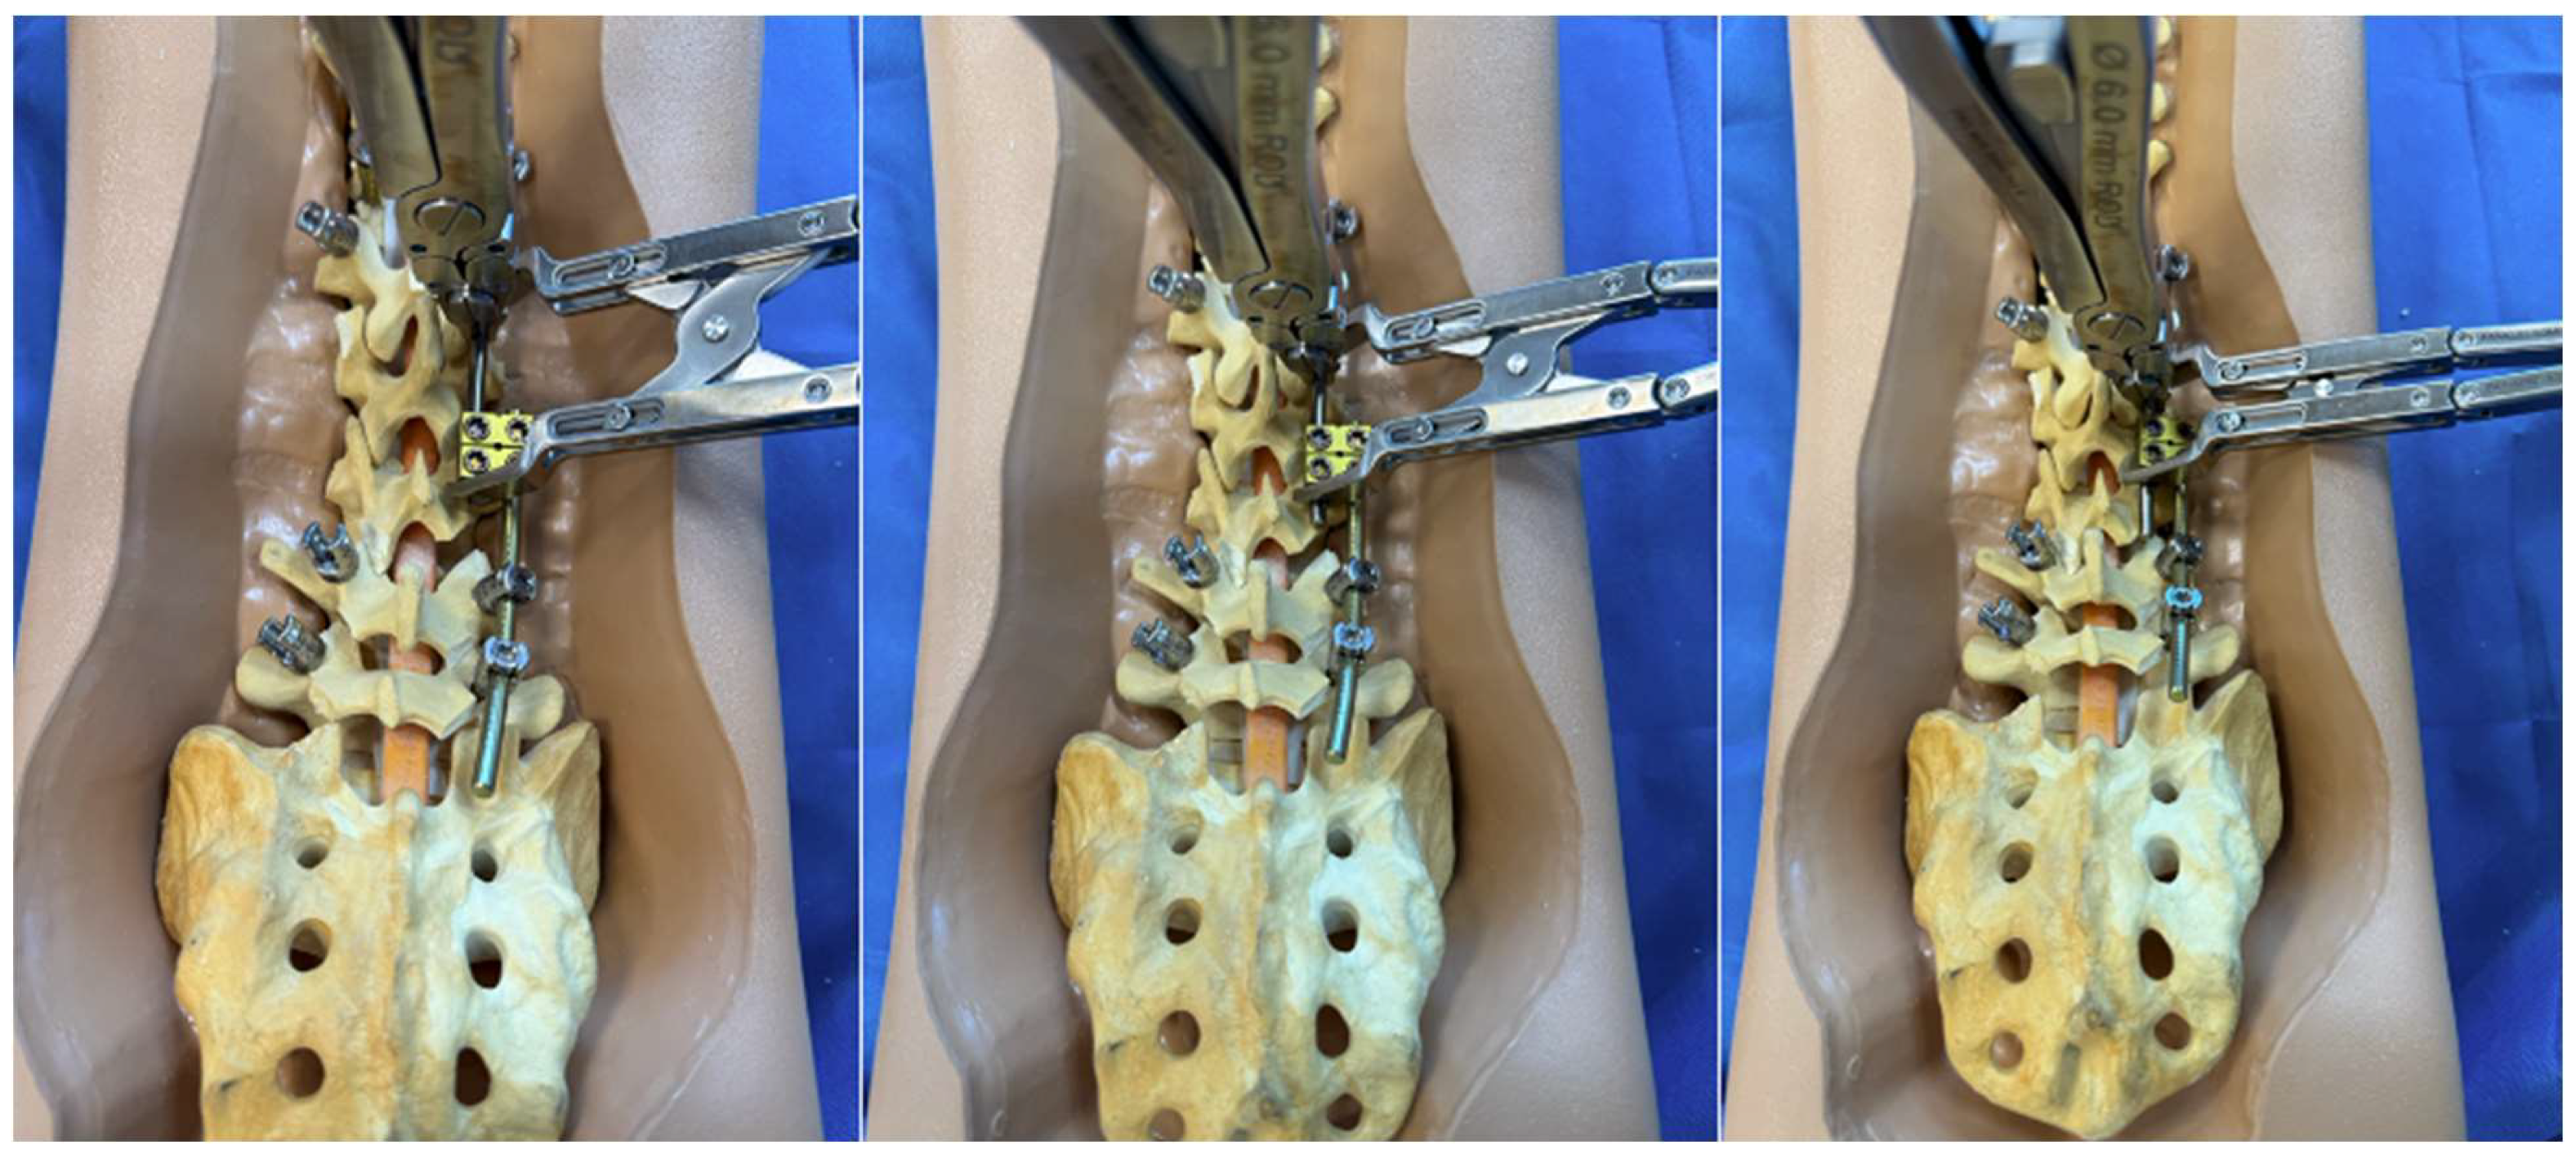

A detailed surgical technique guide by Buchowski et al. in 2007 describes temporary internal distraction in a broader context and highlights important considerations, such as preoperative surgical planning, patient positioning, and placement of proximal and distal anchor points [4]. However, this report aims to focus on the placement and configuration of spinal rods for internal distraction or compression utilizing the construct-to-construct technique. To set up the construct-to-construct configuration, one rod is attached to the proximal anchor points and a second rod to the distal anchor points. There should be at least two (or more) anchor points at the proximal and distal ends to set up this technique. This helps prevent plowing of pedicle screws by distributing the distractive and compressive forces across several motion segments along the spine. These rods are joined by one or two lateral domino connectors to complete the construct-to-construct setup. The more overlap of the rods, the more “runway” there is to apply distraction (Figure 1). Conversely, the less overlap that exists between these two rods, the more “runway” there will be to apply compression (Figure 2). If internal distraction is desired, this construct-to-construct configuration will need to be set up on the concavity of the scoliosis curve. Alternatively, the construct-to-construct configuration will need to be set up on the convexity of the scoliosis curve if internal compression is needed. Distraction or compression is then applied to these rods in a serial, “click-by-click” fashion after loosening the ipsilateral set caps on the domino connectors. Rod grippers may be used to distract or compress against instead of utilizing pedicle screw tulips in order to reduce loosening of the anchor points. After the desired amount of deformity correction is achieved, the set caps on the domino connectors are tightened to hold the correction.

3.3. Traditional Growing Rods

The construct-to-construct internal distraction technique is the most common configuration for traditional growing rod constructs (Figure 6). The distal anchor points comprise two-level pedicle screw fixation. The last spinal level will represent the lower instrumented vertebra of the final fusion construct. The proximal anchor points may be either upgoing rib hooks or pedicle screws. We prefer pedicle screw fixation at upper instrumented vertebra, upper instrumented vertebra-1, and occasionally upper instrumented vertebra-2. It is important to keep in mind that these proximal pedicle screws will experience significant distraction forces with serial lengthening that could loosen the screws at the time of the final spinal fusion. A long titanium rod is passed under the muscle layer to engage into the proximal anchor points. The distal segment of this rod is connected to a lateral domino connector with significant overlap to allow for serial distraction in the future. A shorter rod is tunneled through the domino connector and engaged to the distal anchor points. A rod gripper is used to engage the longer, proximal rod approximately 1 cm above the domino connector (Figure 3). The set cap on the domino connector is loosened, and a distractor is placed between this connector and the rod gripper. Gradual distraction is applied in a controlled, “click-by-click” manner before the set cap is tightened to hold the correction.

Figure 1. Sawbone model utilizing a construct-to-construct internal distraction technique showing the greater overlap of the rods across the lateral domino connectors, the more “runway” there is to apply distraction.